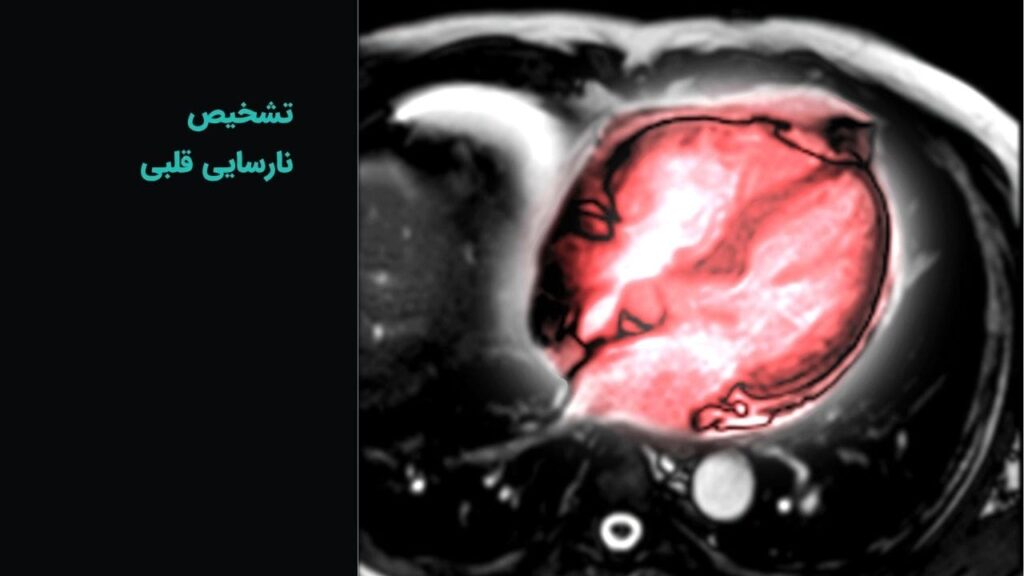

ام آر آی

ام آر آی عمومی و تخصصی با دستگاه 1.5 تسلا